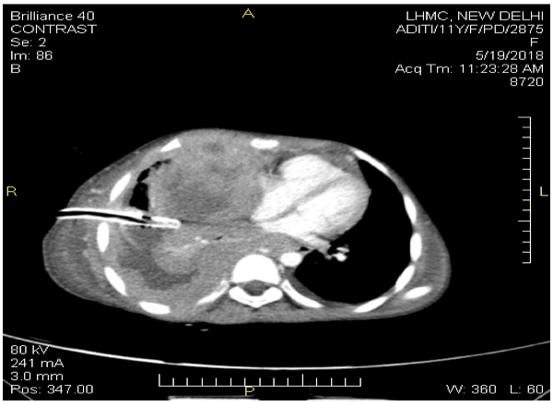

In addition, bone marrow aspirate was performed and was negative for malignant cells. A cardiocentesis was performed thereafter and the fluid was sent again for cytology. The pericardial fluid showed a similar picture as the pleural fluid with a total cell count of 42x109 /L. The cytospin smears revealed the presence of atypical lymphoid cell population which was similar to the pleural fluid smears. A CECT chest was performed thereafter, which showed the evidence of a heterogeneously enhancing soft tissue density mass measuring 7.5x8.9x10.4 seen in the anterior mediastinum involving and infiltrating the anterior chest wall (Figure 4).

Figure 4: CECT Chest: Heterogeneously enhancing soft tissue density mass measuring 7.5x8.9x10.4 seen in the anterior mediastinum involving and infiltrating the anterior chest wall.